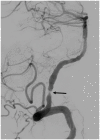

In this review article, we summarized the current advances in rescue management for reperfusion therapy of acute ischemic stroke from large vessel occlusion due to underlying intracranial atherosclerotic stenosis (ICAS). It is estimated that 24-47% of patients with acute vertebrobasilar artery occlusion have underlying ICAS and superimposed in situ thrombosis. These patients have been found to have longer procedure times, lower recanalization rates, higher rates of reocclusion and lower rates of favorable outcomes than patients with embolic occlusion. Here, we discuss the most recent literature regarding the use of glycoprotein IIb/IIIa inhibitors, angioplasty alone, or angioplasty with stenting for rescue therapy in the setting of failed recanalization or instant/imminent reocclusion during thrombectomy. We also present a case of rescue therapy post intravenous tPA and thrombectomy with intra-arterial tirofiban and balloon angioplasty followed by oral dual antiplatelet therapy in a patient with dominant vertebral artery occlusion due to ICAS. Based on the available literature data, we conclude that glycoprotein IIb/IIIa is a reasonably safe and effective rescue therapy for patients who have had a failed thrombectomy or have residual severe intracranial stenosis. Balloon angioplasty and/or stenting may be helpful as a rescue treatment for patients who have had a failed thrombectomy or are at risk of reocclusion. The effectiveness of immediate stenting for residual stenosis after successful thrombectomy is still uncertain. Rescue therapy does not appear to increase the risk of sICH. Randomized controlled trials are warranted to prove the efficacy of rescue therapy.